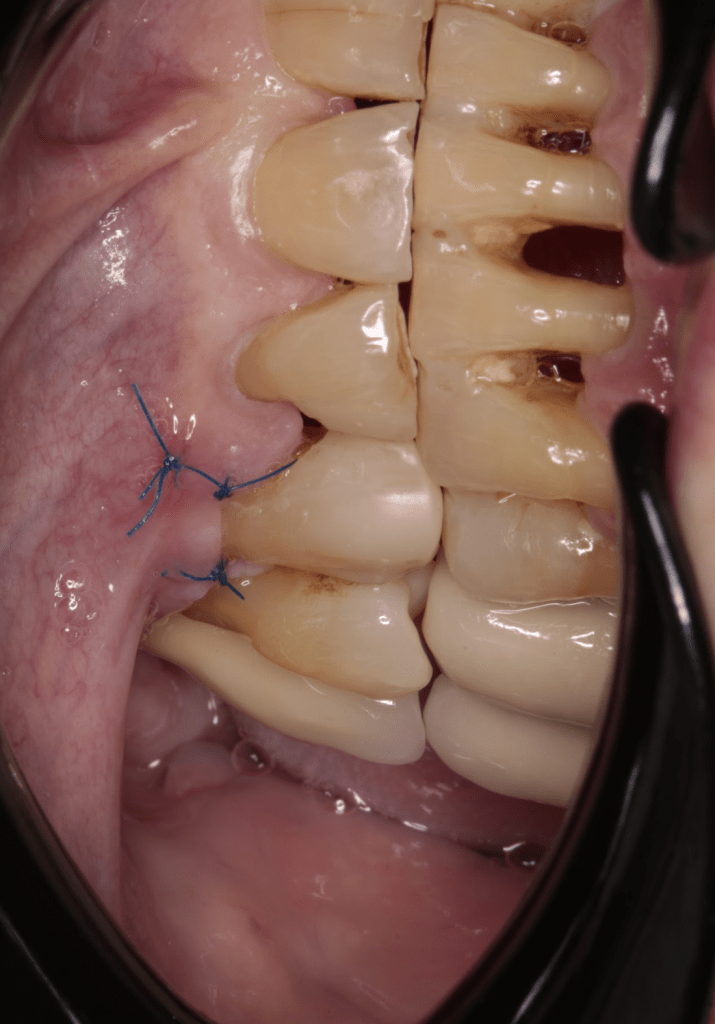

Gingivectomía +reco preendo +reconstrucción

Reco preendo + gingivectomía